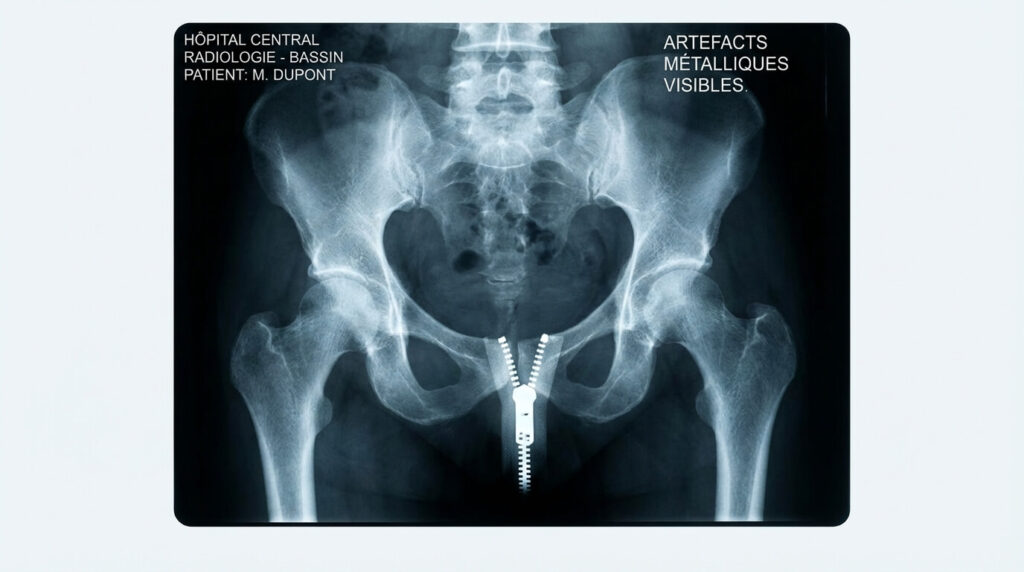

- 👖 Le bas : Oui, il faut généralement retirer pantalon, jupe, ceinture et tout vêtement couvrant le bassin. Les tissus épais (jean, velours) ou les éléments métalliques (zip, bouton) créent des « artefacts » qui gâchent l’image.

Pour comprendre la nécessité de se déshabiller, il faut comprendre le fonctionnement des rayons X. Ces ondes traversent le corps pour imprimer l’image de l’os sur le capteur numérique situé derrière vous. Tout obstacle présent sur le trajet peut apparaître sur l’image finale. L’ennemi numéro un est le métal. Les fermetures éclair (zips), les boutons de jeans, les agrafes de jupes, les ceintures ou même les petits rivets des poches sont totalement opaques aux rayons X. Ils apparaissent en blanc éclatant sur la radio, risquant de cacher une fracture fine, une tumeur osseuse ou un signe d’arthrose situé juste derrière.

Mais le métal n’est pas le seul problème. Certains tissus épais, comme les coutures de jeans, les élastiques serrés ou les broderies denses, peuvent créer des « artefacts » ou des ombres fantômes. Pour le radiologue, qui cherche parfois des anomalies de l’ordre du millimètre (micro-fissures), ces ombres parasites peuvent rendre l’interprétation douteuse ou impossible, obligeant à refaire le cliché et donc à irradier le patient une seconde fois inutilement. C’est pour éviter cela que le principe de précaution « on enlève tout le bas » est souvent appliqué.